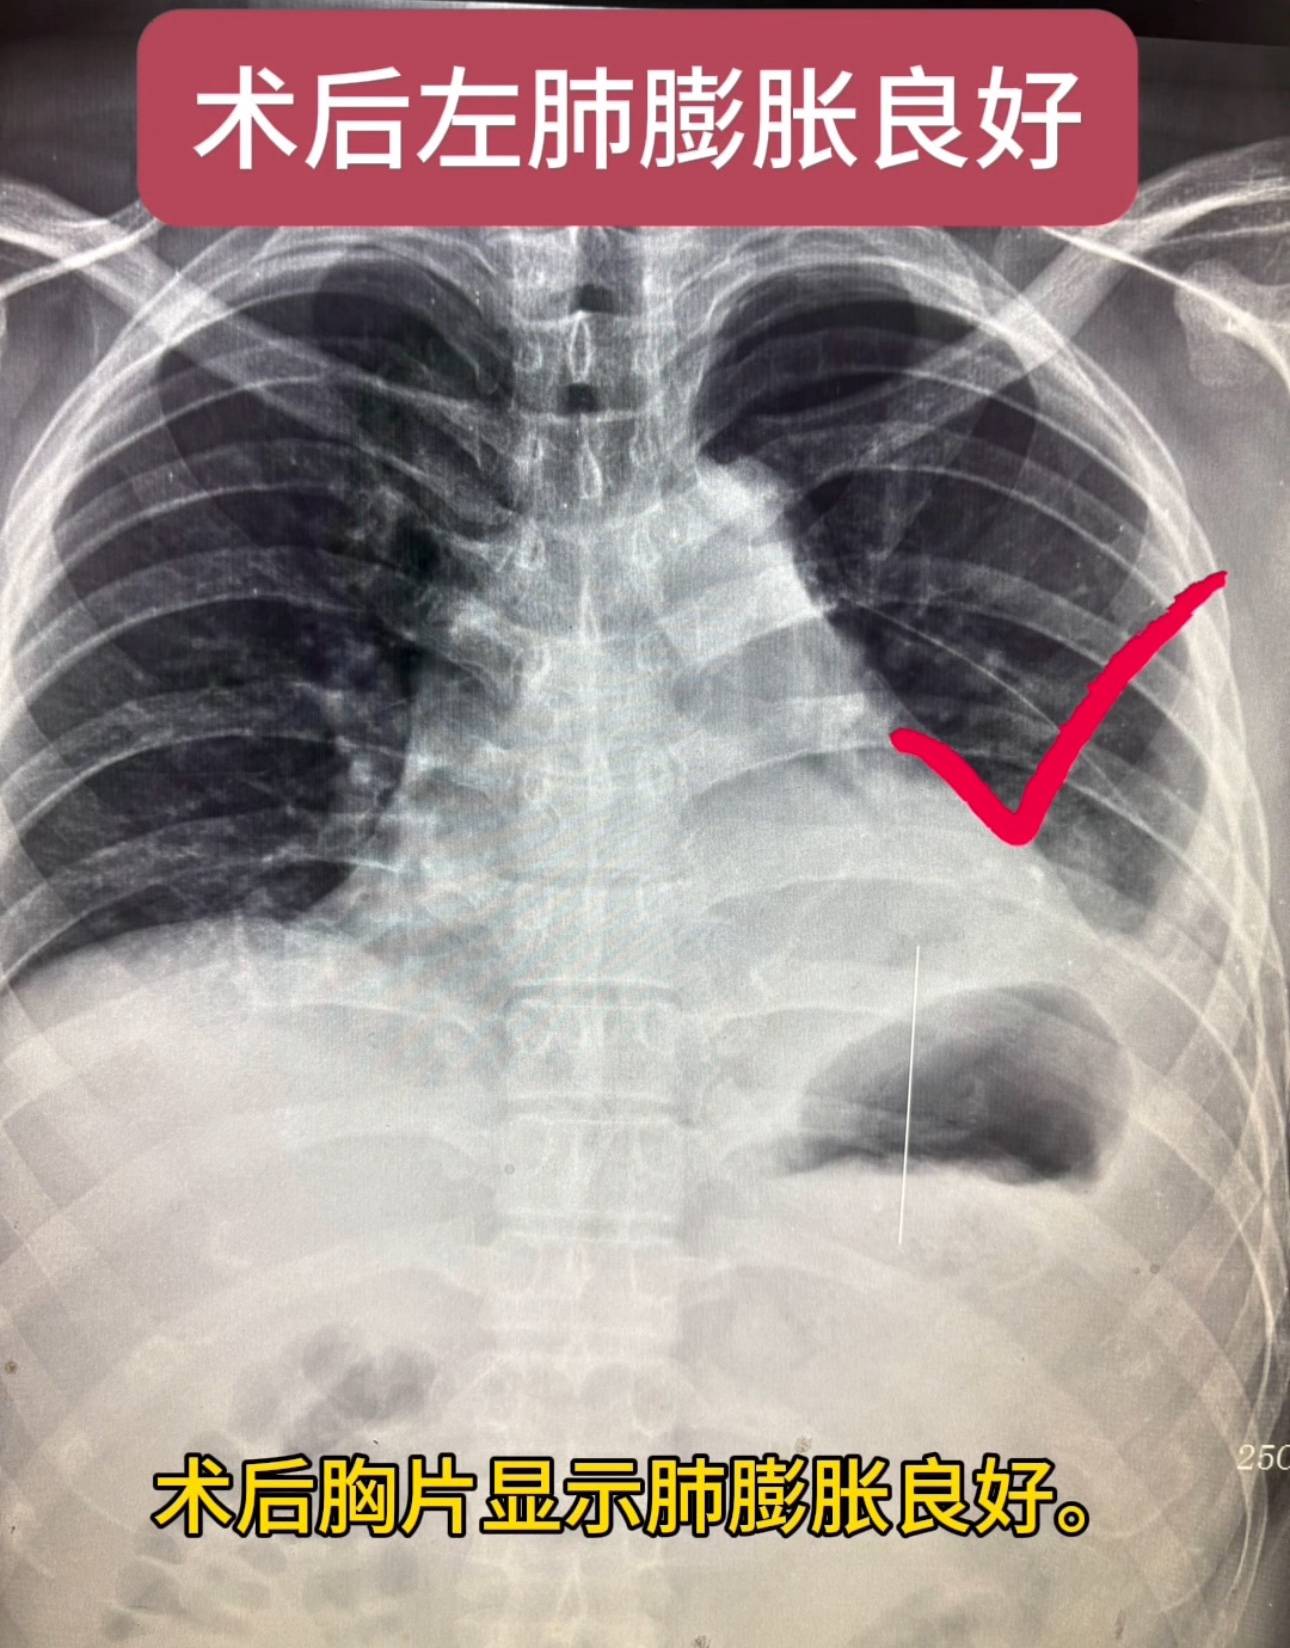

患者男性,34岁,已婚。检查发现肺结节1个月。患者1个月前检查发现左下肺结节,病程中患者无咳嗽咳痰,无胸痛胸闷,牵拉临近胸膜,大小约16×12毫米,考虑为高危倾向你予以抗炎对症治疗,后复查胸部CT发现,左肺下叶后基底段实性结节,较之前变化不明显,术后病理显示为低分化腺癌,术后胸片显示肺膨胀良好。